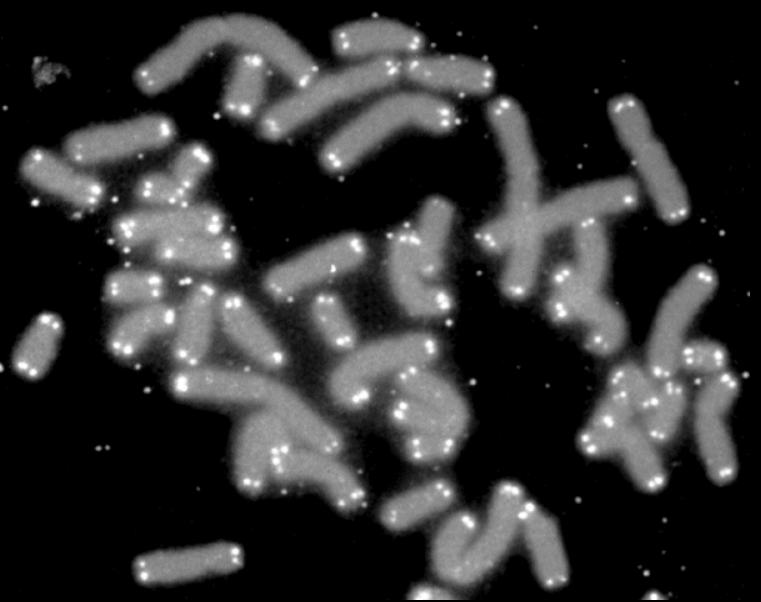

ATM contrôle les réponses aux dommages de l’ADN lors de la formation d’une cassure double brin de l’ADN. Il phosphoryle les histones de type H2AX sur la sérine 139 pour former γ-H2AX. Cette forme d’histone permet d’obtenir de l’ADN moins condensé ce qui facilite le recrutement des enzymes de réparation (Paull et al., 2000). La perte d’activité de la kinase ATM ou l’hétérozygotie pour les variants pathogènes du gène ATM augmentent les risques de cancer (Choi et al., 2016). La forme γ-H2AX n’est pas forcément précisément localisé strictement au point de la cassure double brin mais peut être présente jusqu’à plusieurs mégabases autour. Il y a ainsi une amplification du signal d’alerte.

L’instabilité du génome peut aussi provenir de dysfonctionnements de la mitose si les chromosomes ne sont pas répartis correctement entre les deux cellules-filles ce qui peut mener à une aneuploïdie : un nombre anormal de chromosomes dans les cellules. Cela peut être la conséquence par exemple de défauts dans la duplication du centrosome pendant la phase S menant à des fuseaux mitotiques multipolaires.

Des niveaux élevés d’aneuploïdie sont associés à un mauvais pronostic, notamment par une réponse immunitaire antitumorale réduite (Davoli et al., 2017). De plus, les chromosomes présentant davantage d’oncogènes et moins de gènes suppresseurs de tumeurs sont plus fréquemment amplifiés dans les cancers, c’est-à-dire les chromosomes 7, 8, 12, 13 er 20, les chromosomes 12 et 13 étant les plus fréquemment amplifiés, sans doute la résultante d’une pression de sélection (les aneuploïdies se font au hasard, mais certaines sont plus avantageuses que d’autres selon le contexte) (Davoli et al., 2013). Les tumeurs issues de différents tissus présentent des profils d’aneuploïdie spécifiques susceptibles de conférer aux cellules tumorales des avantages sélectifs particuliers à chaque type cellulaire (Sack et al., 2018).